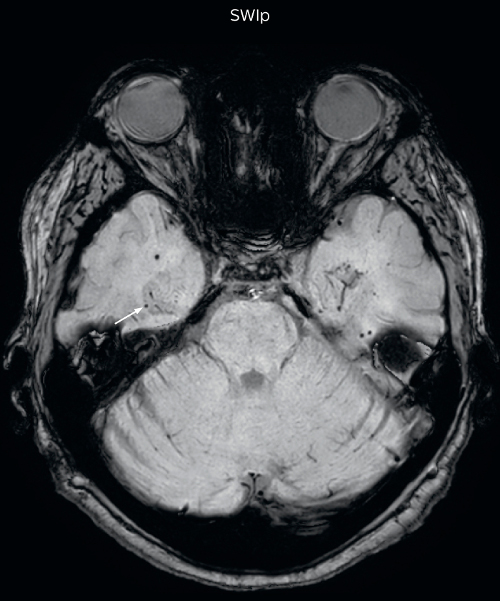

The SWIp sequence offers high resolution 3D susceptibility weighted brain imaging, which helps to visualize deoxygenated blood or calcium deposits. In combination with other clinical information, it may help in the diagnosis of various neurological pathologies

“With SWIp we are basically looking for blood byproducts. It is a sensitive method for visualizing small lesions containing deoxygenated blood. In our comparison, SWIp images are vastly better than gradient echo imaging, there’s no question of that anymore.” “We find the SWIp images very useful in three areas in particular. In patients with a history of hypertension, it offers clear visualization of hemosiderin deposition from hypertensive hemorrhages. We certainly see a greater number of foci of hemosiderin deposition on the SWIp images than on the T2* gradient echo images. In addition, it also helps us visualize amyloid depositions in patients with amyloid angiopathy.” Dr. Nickerson mentions trauma patients are the third large area where SWIp is useful. “We benefit from SWIp in trauma patients, certainly in cases with diffuse axonal injury and shearing injuries. Our study shows that SWIp usually provides us better visualization,” he says. “Apart from these three, SWIp also helps us to beautifully depict the normal venous anatomy in patients with venous outflow issues or vascular congestion. In some cases, we have seen downstream effects of arterial problems. And in patients with vascular malformations we have seen deposition of blood products associated with those.”

“We switched over entirely. SWIp is now included in all our routine brain exams. We developed two different SWIp sequences: a high spatial resolution (0.5 x 0.5 mm) version that takes 5.5 minutes and our fast SWIp that takes just three minutes. Only in patients that are moving tremendously we occasionally still acquire a gradient echo sequence.” “For us, SWIp use has resulted in more diagnostic confidence when small lesions, such as small shear injuries, vascular malformations, or minute amounts of calcification, need to be detected,” says Dr. Nickerson. “Our physicians greatly value the SWIp images. When we get patients transferred from other facilities with SWIp missing from their exam, we have several neurologists and neurosurgeons who order a new MRI exam because they want to see the SWIp images.”

Gradient echo imaging and SWIp are compared in a patient with radiation-induced foci of hemosiderin deposition. A greater number of small foci is seen on the SWIp image. Ingenia 3.0T